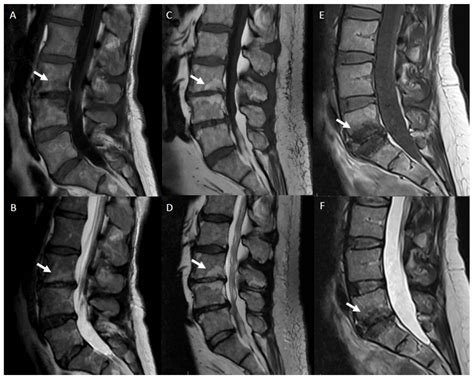

Recognizing the symptoms of conditions that are degenerative in the spine is crucial for early intervention. While some individuals may have significant findings on an X-ray or MRI without feeling much pain, others may experience debilitating discomfort. Common indicators include:

⚠️ Note: Always consult with a qualified medical professional for an accurate diagnosis. Imaging tests like MRI or CT scans are necessary to confirm if your symptoms are truly caused by changes that are degenerative in the spine.